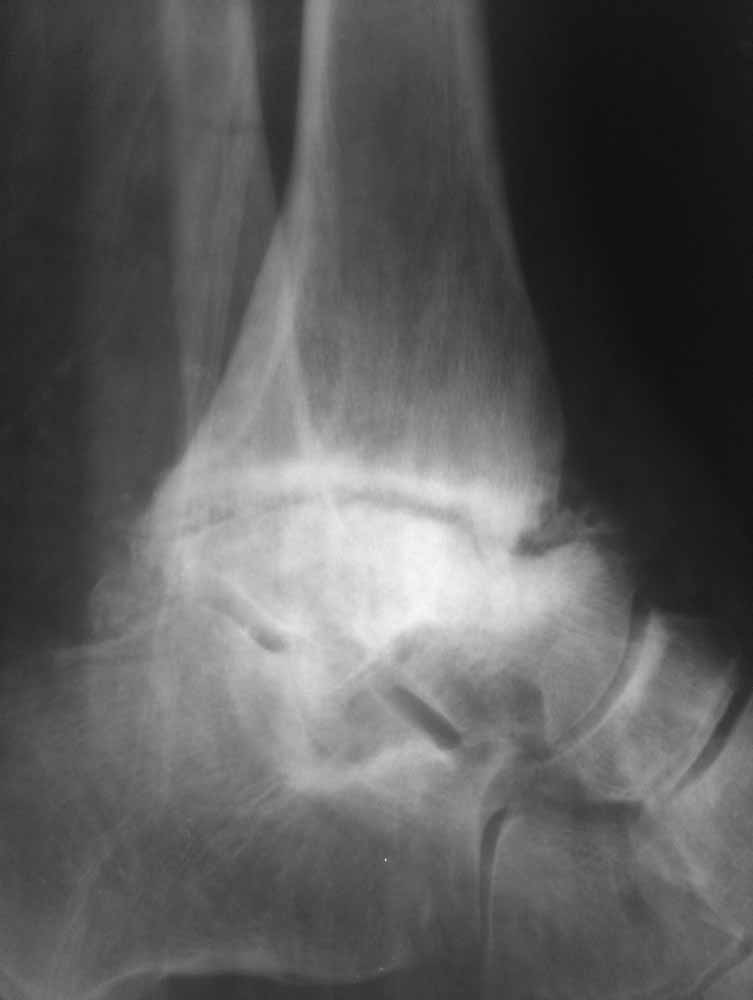

Re: Дефартроз голеностопа+перелом пилона+перелом тарана?

Жалобы со стороны второго сустава есть - прыгать на костылях до томографа без опоры на левую стопу пациенту было больно.

Зачем вытяжение - эффект на рентгенограммах виден.

Склоняемся к мысли, что все таки Charcot's Joint.

Планируем артродез стержнем правого голеностопа + аппарат на левый голеностоп.

Остается вопрос - как монтировать ? одномоментно корректировать или все таки постепенно аппаратом?